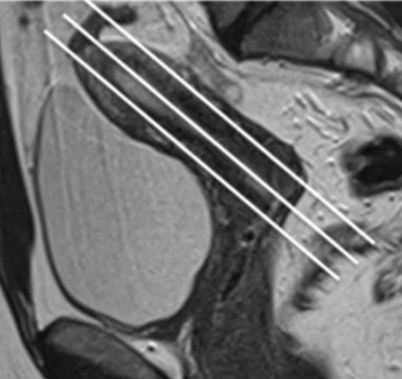

Tous les protocoles incluent des séquences d’IRM en T1 avec ou sans Fat Sat, toujours en axial avec ajout de plan sagittal quelquefois. De même, des séquences T2 multiplanaires du bassin en orientation strictement axiale, sagittale et / ou coronale sont toujours réalisées, ainsi que des séquences orientées par rapport à l’utérus. Ces dernières sont plus couramment obtenues par une combinaison de vrais coronaux et vrais axiaux du fond et du corps de l'utérus. La séquence 3D-T2 du bassin, permettant le reformatage multiplanaire (MPR) de l'utérus, est quelquefois utilisée bien que cette séquence fasse l’objet d’une qualité de d'image faible.

Les auteurs de cette étude remarquent que les capacités multiplanaires et la bonne résolution pour les tissus mous de l'IRM fournissent une excellente évaluation du large spectre de manifestations radiologiques des FGTCA. Un protocole d'imagerie normalisé et une un compte rendu uniformisé garantissent, dans ce cadre, une mise en lumière de ces résultats, contribuant à un diagnostic et à une classification corrects des FGTCA, des pathologies associées et de leurs complications.